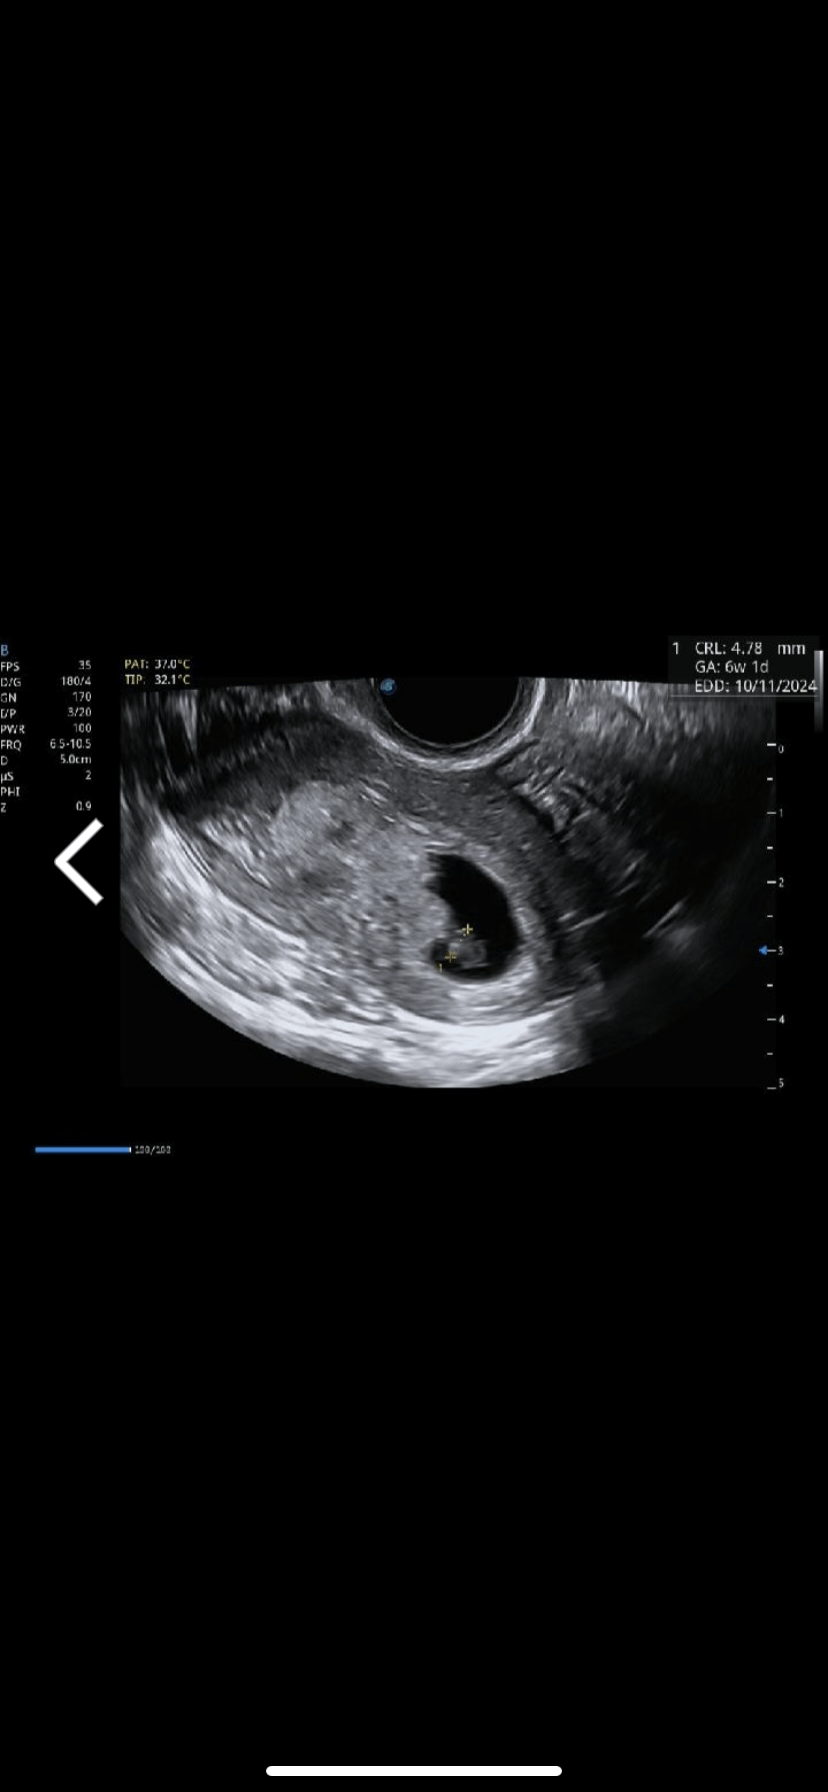

Vážená paní doktorko, ráda bych Vás požádala o odborný názor k pravděpodobnosti oplodnění v následující situaci. Poslední menstruace proběhla 3.–6. 11., jednalo se o cyklus po biochemickém těhotenství. Dne 26. 11. byl proveden digitální ovulační test Clearblue, který vyšel pozitivní (symbol úsměvu). Test byl proveden kolem 16. hodiny, přičemž přibližně od 15. hodiny se objevily pro mne typické ovulační bolesti/ tlak ve vaječnících, které běžně s ovulací mívám. Pohlavní styky s manželem proběhly dne 22. 11., 24. 11., 25. 11. a 26. 11. Existuje také hypotetická možnost pohlavního styku dne 21. 11. ve večerních hodinách (cca 5 dní před pozitivním ovulačním testem), nicméně si tuto událost nejsem schopna s jistotou vybavit a dotyčná osoba uvedla, že k pohlavnímu styku nedošlo. Dne 23. 12. bylo ultrazvukem potvrzeno těhotenství s nálezem odpovídajícím stáří 5+0, tedy v souladu s ovulací kolem 26. 11. Chtěla bych se Vás proto zeptat, jaká je reálná klinická pravděpodobnost, že k oplodnění došlo spermiemi ze dne 21. 11. a naopak jaká je pravděpodobnost, že k oplodnění došlo spermiemi z pozdějších dní, kdy proběhly opakované styky těsně před ovulací a v den ovulace. Uvědomuji si, že spermie mohou v ideálních podmínkách přežít i delší dobu, nicméně bych velmi ocenila praktický lékařský pohled na tuto situaci z hlediska běžné gynekologické praxe. Ještě bych ráda doplnila, že mám velice nepravidelný cyklus s rozmezí 25 - 50 dní. Předem Vám velmi děkuji za Váš čas a odpověď.